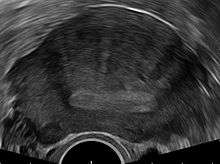

The uterus may be imaged using transvaginal ultrasound (US) or magnetic resonance imaging (MRI). Transvaginal ultrasound is the most cost effective and most available method. The diagnostical features are:[20][21]

- a globular enlarged uterus

- anterior/posterior wall asymmetry

- myometrial cysts

- linear, acoustic shadowing without presence of myoma

- diffuse myometrial echogenicity

- sign of endometrial invasion to the myometria

The junction zone (JZ) may be assessed by three-dimensional transvaginal ultrasound (3D TVUS) and features of adenomyosis are disruption, enlargement or invasion of the junctional zone.[22]